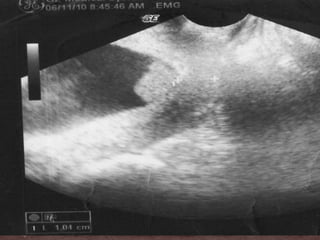

 USG en sala:

 longitud cervical de 1.04   cm

 presencia de SLUDGE

 Se inicia cobertura antibiótica